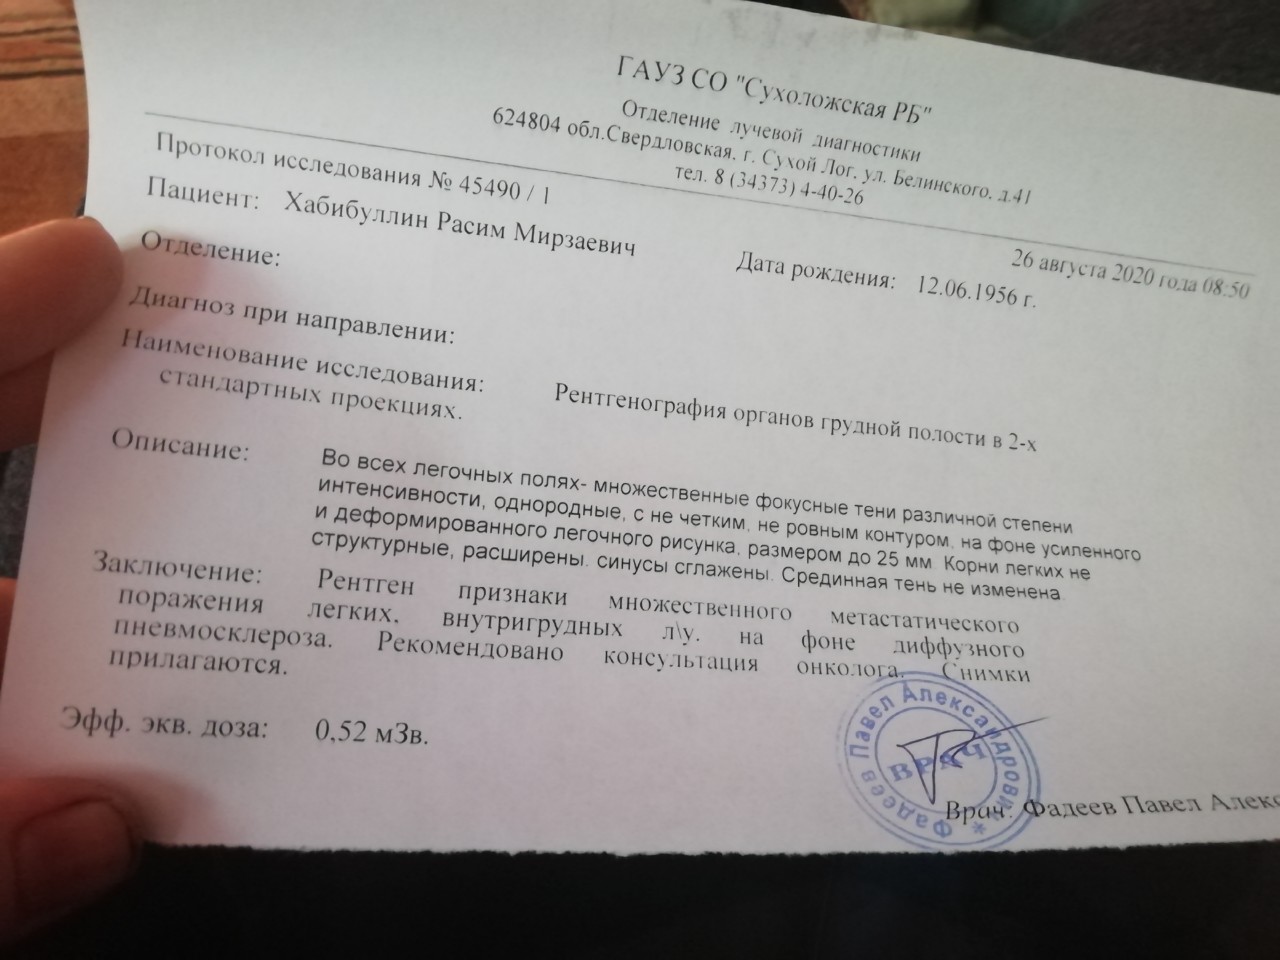

Фотографии рентгеновских снимков без необходимости направления от врача